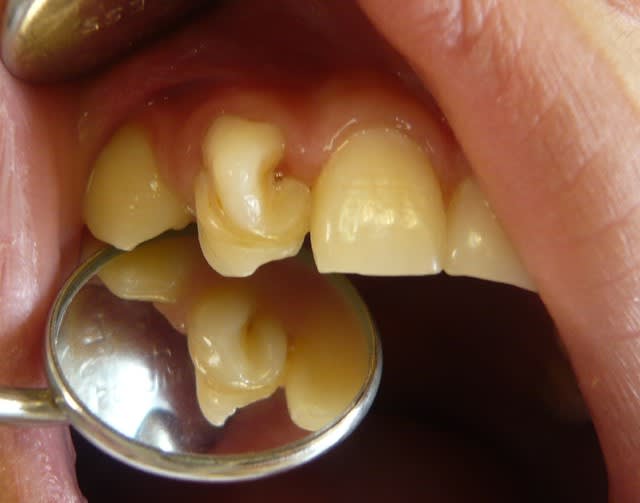

Voici un enfant de 10 ans et demi.

Comment envisageriez vous le traitement et l'avenir de cette incisive latérale? Les moyens financiers des parents de cet enfant sont inexistants...

Si absolument aucun moyen financiers : plasties a minima, et sculpture au composite avec un compromis entre forme initiale et forme idéale pour tenter de ne pas éfracter.

Quand il sera plus grand, on pourrait envisager d'ouvrir pour explorer le système canalaire qui n'a pas l'air trop bizarroïde au niveau radiculaire en tout cas, puis couronne.

le 1er danger c'est l'infiltration au niveau du sillon jusqu'à provoquer une atteinte pulpaire

dc tu scelles en urgence au sealant et au flow

ensuite effectivement compo pr attenuer la morphologie atypique

si possible par la suite couronne(personne ne fait du cerec par chez toi? et aurait envie de faire sa BA de l'année)

j'eviterai de traiter et resterai sur dent vivante,le traitement n'etant pas si simple sur ce type de dents qui a svt des canaux très atypiques